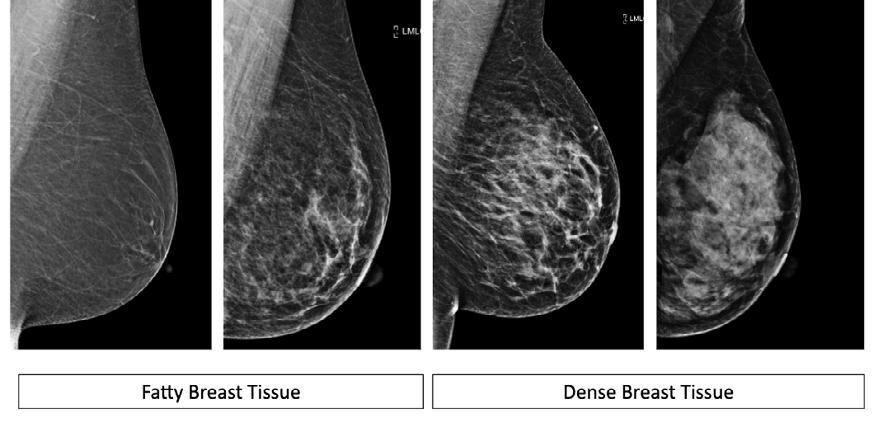

October is breast cancer awareness month. Breast cancer affects 1 in 9 women. With the advances in medical science, many breast cancers, when caught early, have successful outcomes. Accordingly, we should be aware of methods of early detection and treatment. Early detection maximizes the chances of survival. After diagnosis, treatment usually includes surgery, chemotherapy and occasionally radiation therapy. Your treatment team typically includes a Breast Surgeon, Oncologist, Radiation Oncologist, Radiologist, and a Plastic Surgeon. Your Plastic Surgeon is uniquely qualified to help you regain your confidence by minimizing the effects of the cancer treatment on the appearance of your breasts with breast reconstruction.